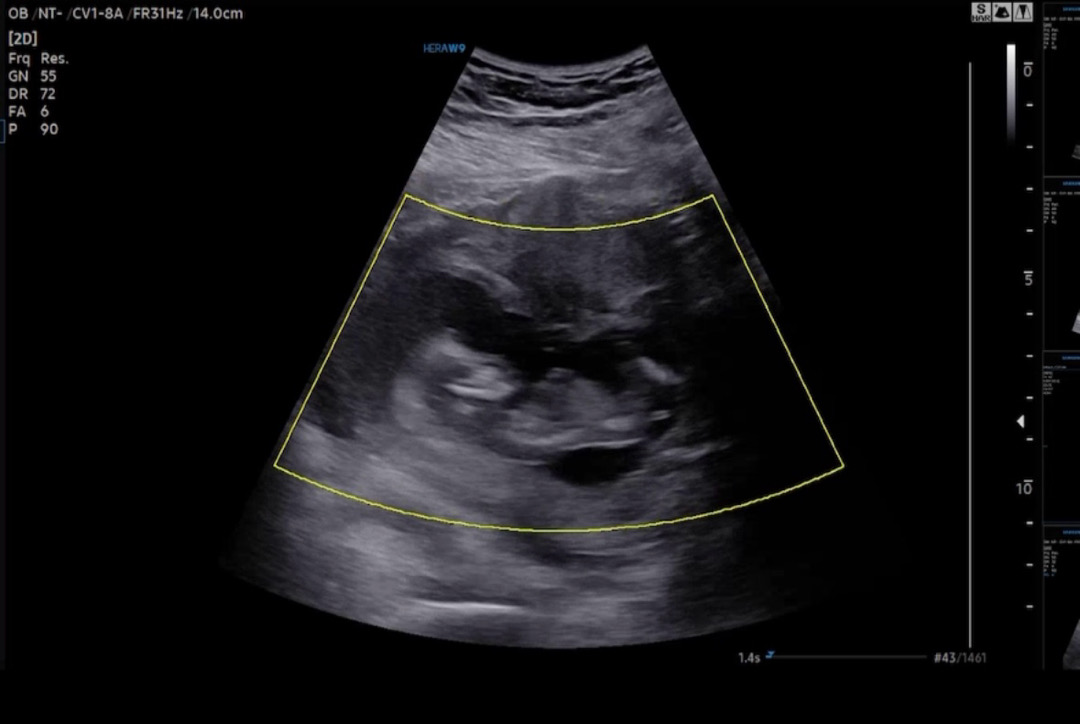

12주 5일차 각도법 궁금합니당 ㅎㅎ

고수님들 어때 보이시나요 ~~? ㅎㅎ

딸같아용~

우왕 너무 신기하네요ㅎㅎ댓글 감사합니다~~